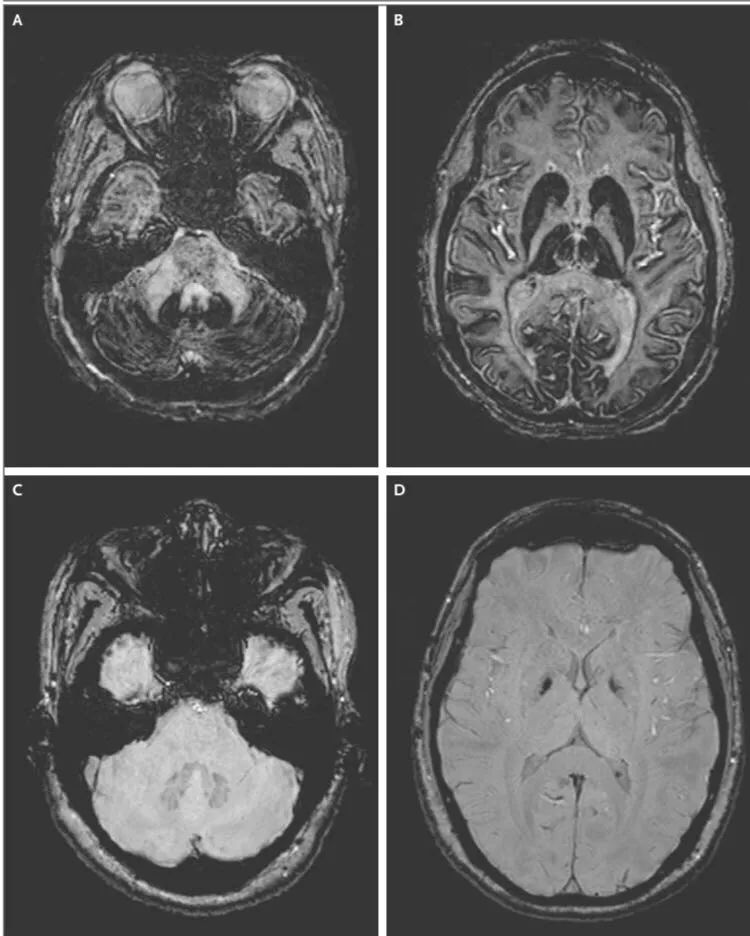

MRI:

小脑,丘脑,壳核和尾状核和肝脏的齿状核在T1和T2加权像呈低信号。

(A、B为患者;C、D为健康对照)